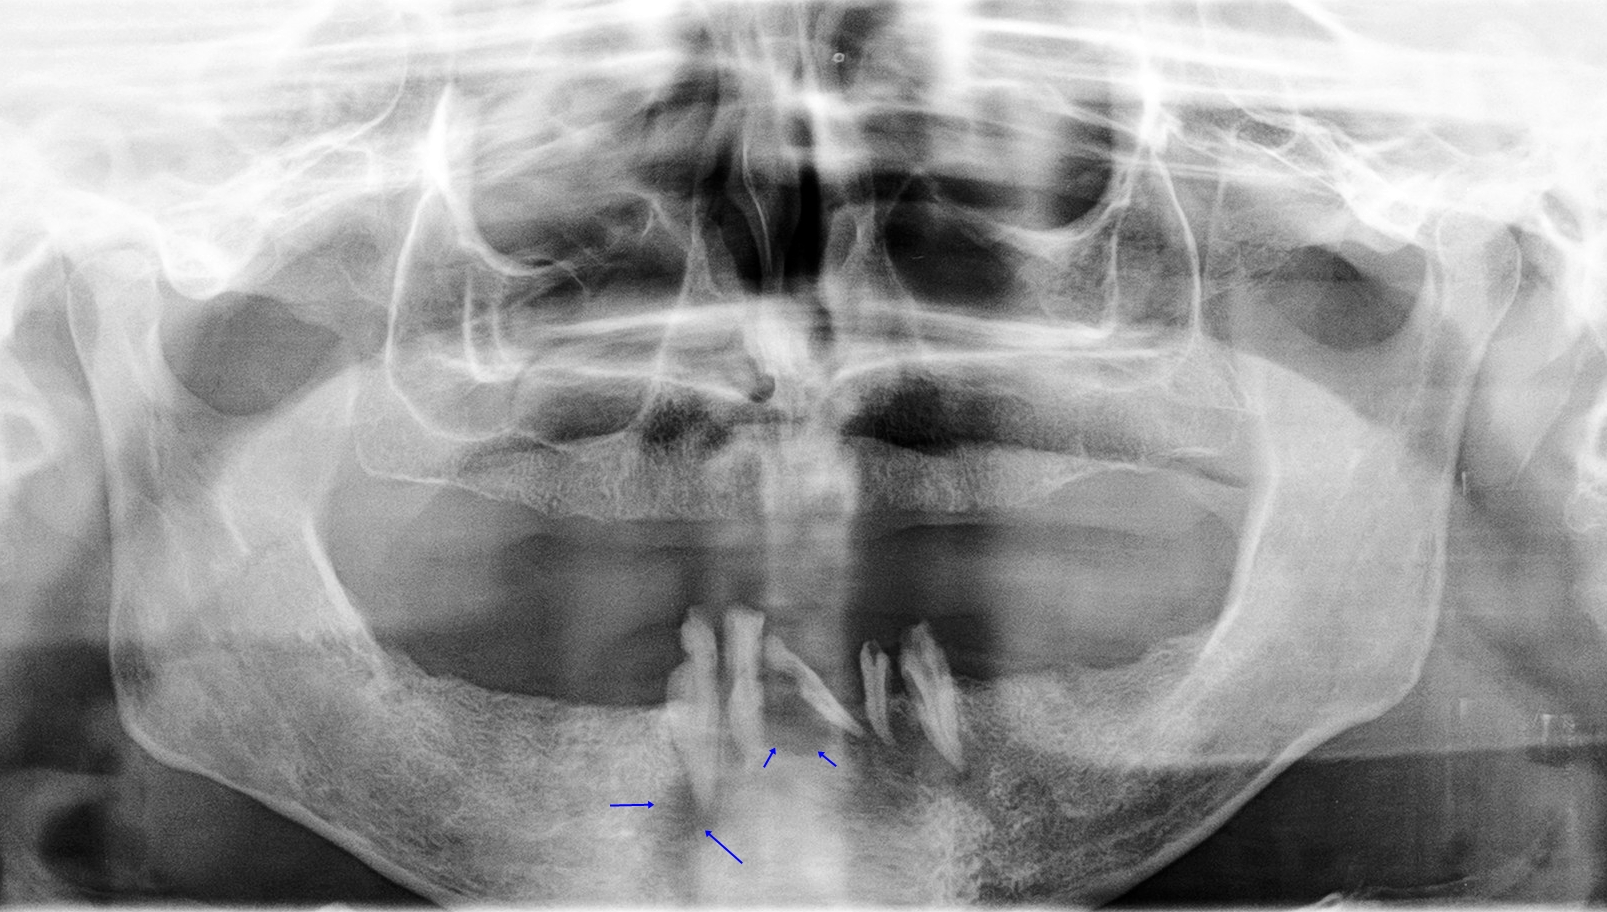

La fistula cutánea odontogénica (FCO) es el resultado de una canalización anormal originada a partir de una infección crónica periapical. Representa todo un reto diagnóstico ya que frecuentemente son lesiones etiquetadas erróneamente como dermatológicas. El diagnóstico diferencial es amplio, incluyendo el granuloma piogénico, tuberculosis cutánea o malformaciones congénitas entre otros. Exponemos el caso de un varón de 46 años diagnosticado de FCO que presentó una rápida mejoría tras exodoncia de las piezas dentales afectas y fistulectomía. Consideramos importante el conocimiento de esta patología para evitar retrasos innecesarios en el diagnóstico y tratamiento adecuado.